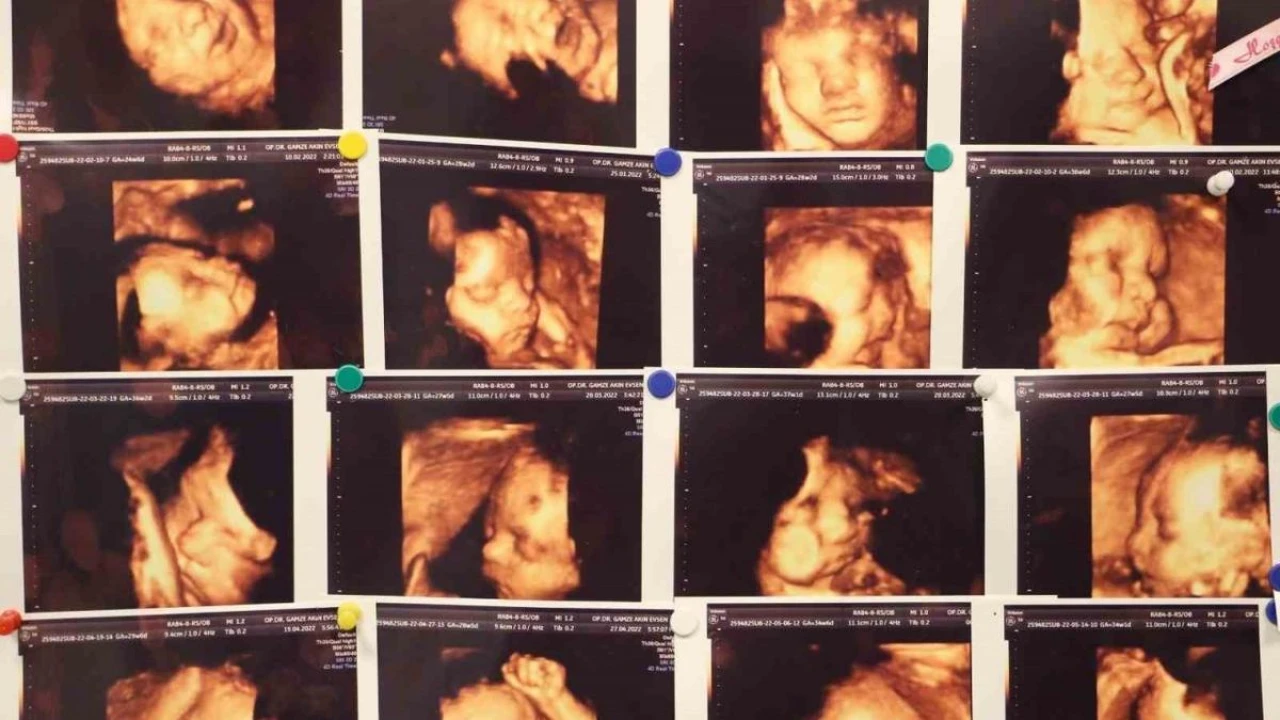

Memorial Hastanesi Kadın Hastalıkları ve Doğum Uzmanı Op. Dr. Gamze Akın Evsen, çocuk sahibi olmaya hazırlanan çiftlerin yaşadığı en büyük travmalardan biri olan gebelik kayıpları, çoğu anne adayının psikolojisinin bozulmasına ve çaresizlik hissine kapılmasına neden olduğunu belirterek, Klinik olarak saptanan gebeliklerin yüzde 10-15'i düşükle sonuçlanmakla beraber bu durumun tekrar etmesi yani tekrarlayan gebelik kayıplarında oran Yüzde 3 ila 5'tir dedi.

Memorial Hastanesi Kadın Hastalıkları ve Doğum Uzmanı Op. Dr. Gamze Akın Evsen, çocuk sahibi olmaya hazırlanan çiftlerin yaşadığı en büyük travmalardan biri olan gebelik kayıpları, çoğu anne adayının psikolojisinin bozulmasına ve çaresizlik hissine kapılmasına neden olduğunu belirterek, "Klinik olarak saptanan gebeliklerin yüzde 10-15’i düşükle sonuçlanmakla beraber bu durumun tekrar etmesi yani tekrarlayan gebelik kayıplarında oran Yüzde 3 ila 5’tir" dedi.

Kadın Hastalıkları ve Doğum Uzmanı Op. Dr. Gamze Akın Evsen, gebelik kayıplarında en sık kromozomal sıkıntılar olmakla beraber, genetik anomaliler, hormonsal sıkıntılar, kan pıhtılaşması, rahmin yapısal bozuklukların olduğunu ve tekrarlayan gebelik kayıplarının ise öncelikle anne ve babanın kronik hastalıkları, tıbbi öyküleri, ailede mevcut genetik hastalıkları gibi durumların ayrıntılı bir şekilde sorgulanmasıyla ortaya çıkacağını söyledi.

Tıbbi literatürde abortus yani düşük olarak tanımlanan gebelik kaybı, bebeğin 500 gram ağırlığına ulaşmadan veya 20’inci haftadan önce çeşitli sebeplerden ötürü gebeliğin sonlanması anlamına geldiğini açıklayan Dr. Evsen, genelde en sık ilk 3 aylık dönemde görülebilmekte olduğunu dile getirdi.